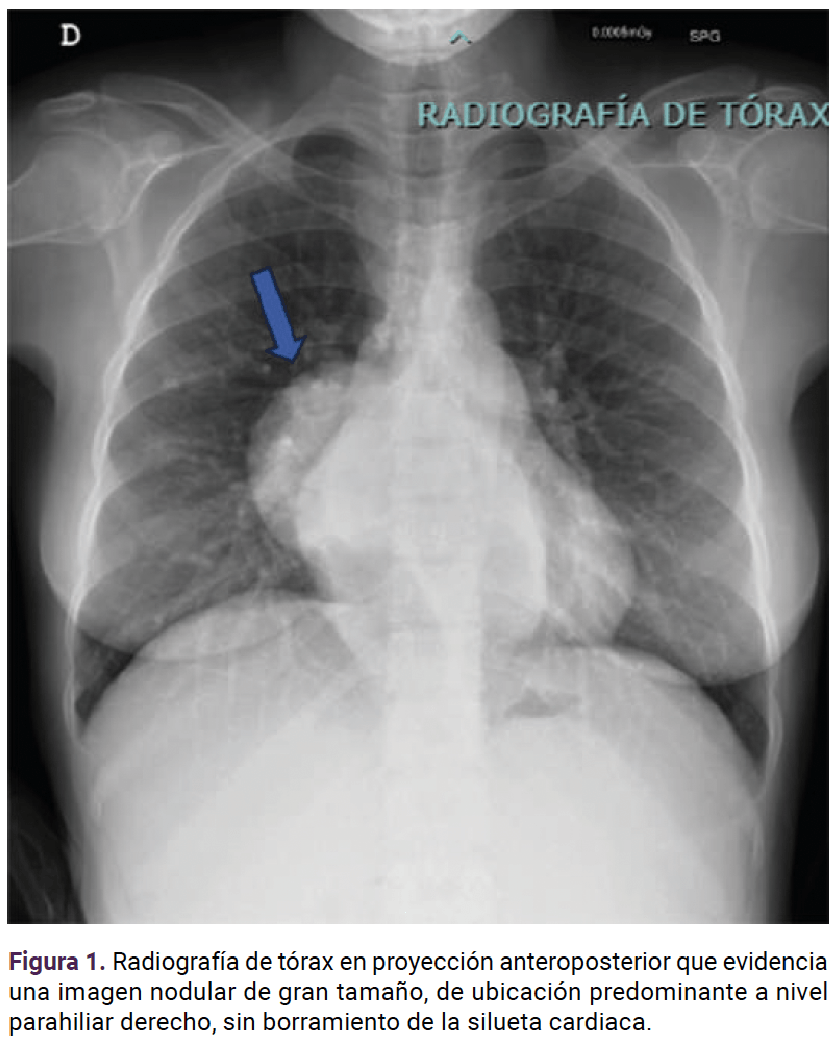

En otra radiografía de tórax se documentó una imagen nodular parahiliar derecha sin borramiento de la silueta cardiaca (Figura 1). Se solicitó una TAC de alta resolución que reportó: masas paravertebrales dorsales bajas a derecha e izquierda quizá correspondientes a adenopatías retrocrurales y nódulo calcificado, en la base del lóbulo superior derecho. Figura 2

<strong>Figura 2</strong>

Figura 2